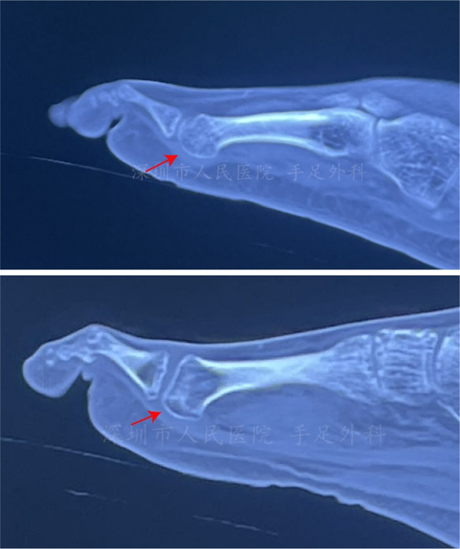

图6:拇趾籽骨

图7:籽骨骨折